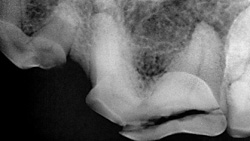

Preoperative radiograph of the maxillary left 4th premolar